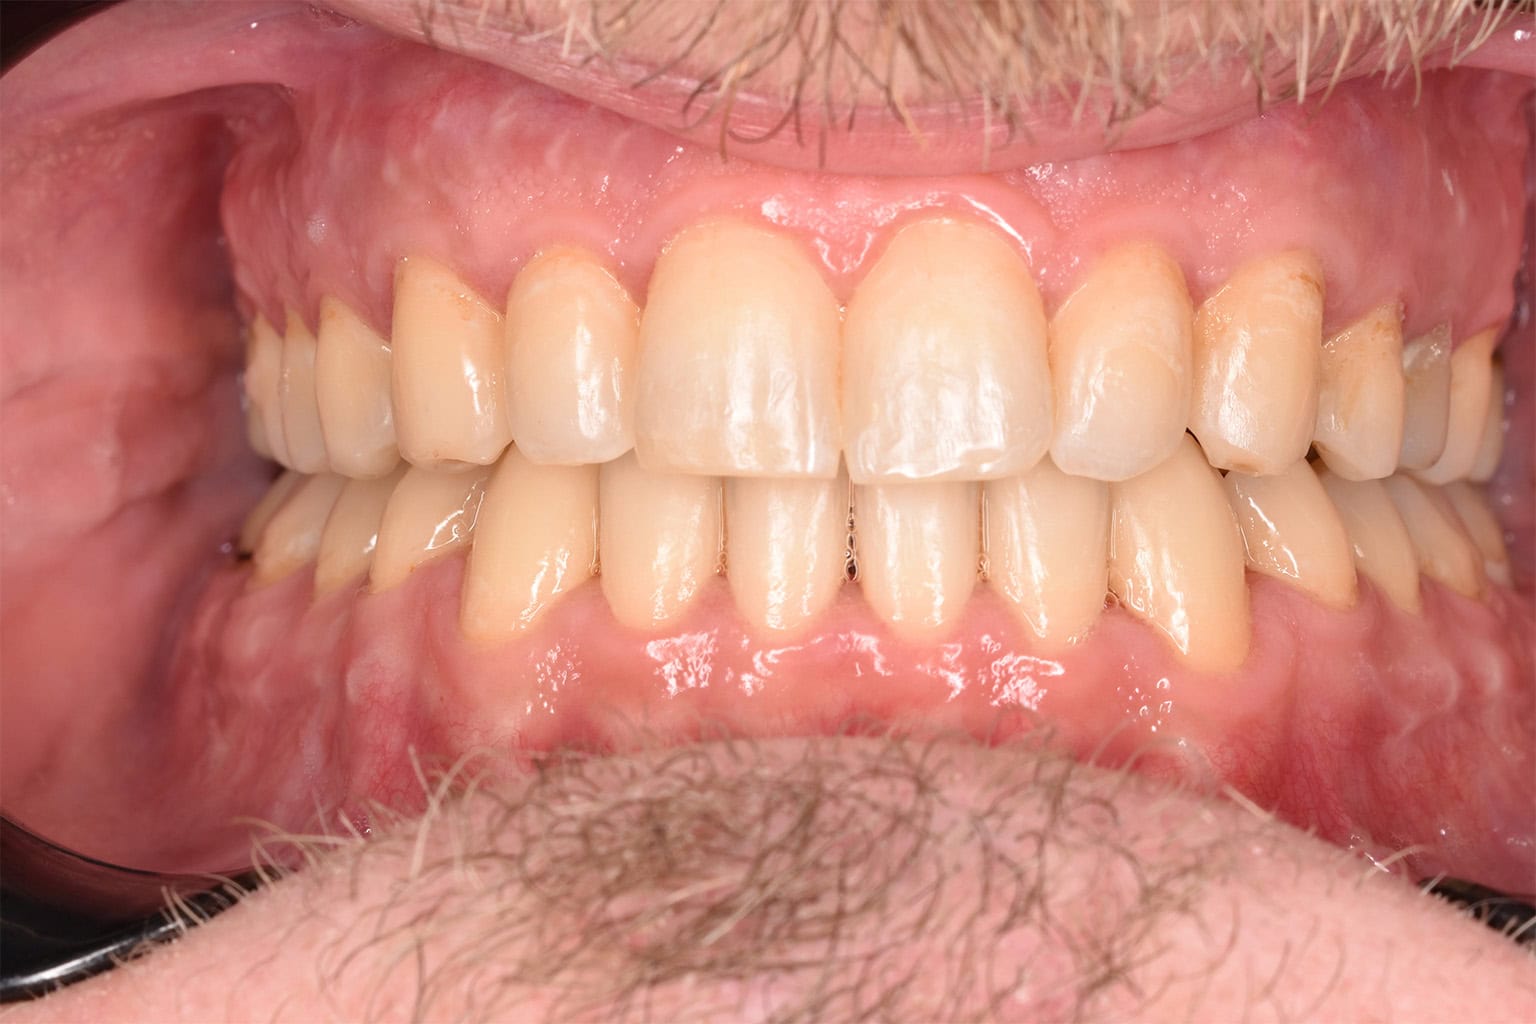

Vorher-Nachher-Ergebnisse

Echte Ergebnisse. Echte Menschen.

Jede Behandlung bei TIEFBLAU Kieferorthopädie ist so individuell wie der Mensch dahinter. In unserer Vorher-Nachher-Galerie zeigen wir Ihnen echte Behandlungsergebnisse aus unserer Praxis in der Kölner Südstadt: Schonend erzielt, präzise geplant und mit dem Anspruch, den wir seit über 40 Jahren an jede Behandlung stellen.

Die Bilder geben Ihnen einen Eindruck davon, was moderne Kieferorthopädie leisten kann, ob bei Kindern, Jugendlichen oder Erwachsenen.

Der sichtbare Unterschied

Dokumentiert. Überzeugend. Nachhaltig.